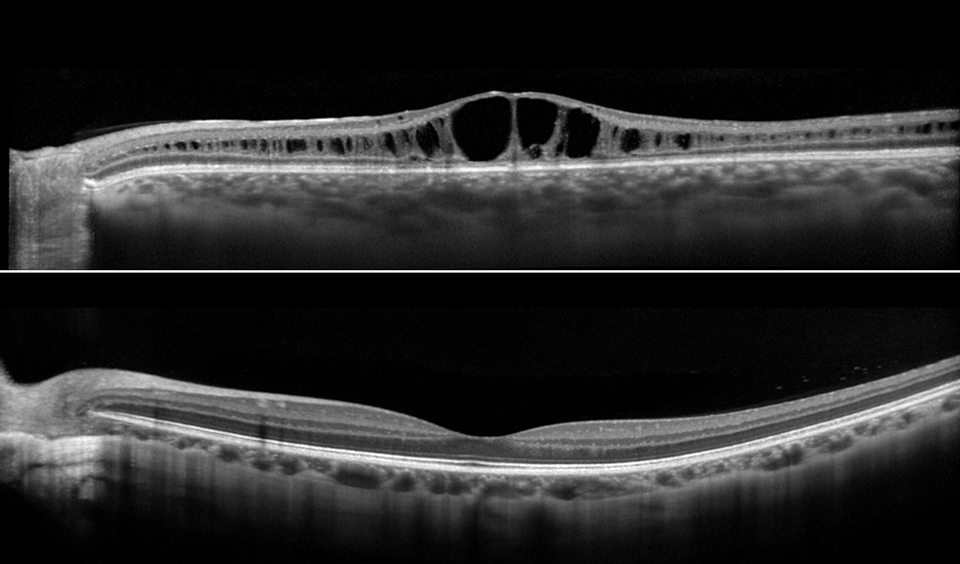

Two OCT scans on top of one another showing a health retina and a diseased retina.

These OCT scans show the difference between a retina that has X-linked juvenile retinoschisis (top) and one that is considered normal (bottom).